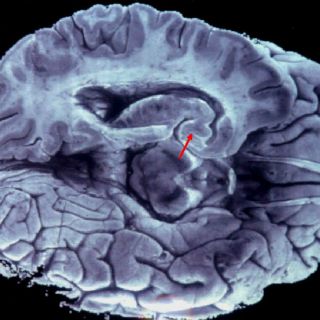

El equipo del ingeniero Tanaka logró este avance a través de mejorar la precisión de la tecnología de espectrometría de masas, lo que permite detectar en la sangre la acumulación de proteínas beta-amiloide, una de las probables causas del Alzheimer al afectar la transmisión entre las células nerviosas del cerebro.

Según las investigaciones, esta proteína se acumula en el cerebro durante un periodo de entre 10 y 15 años antes de que aparezcan los primeros síntomas de la enfermedad.

Al margen de situarse en el cerebro, esta proteína también se acumula en la sangre, aunque en cantidades tan sumamente pequeñas que su identificación resulta muy compleja a través de los ensayos habituales, algo que con la tecnología descubierta por el equipo de Tanaka sí será posible.